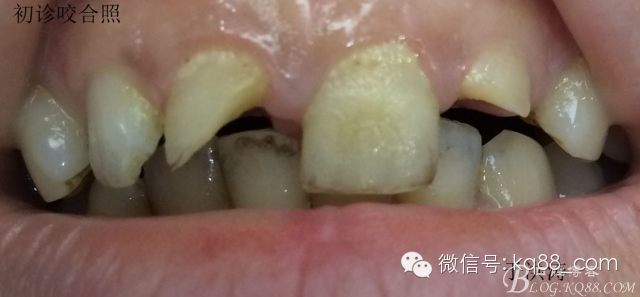

檢查:明顯可見22牙冠橫向斷裂至頸1/3處,近遠中與腭側斷裂至齦下??梢?/span>11牙冠斜向近中斷裂,近中與腭側均斷裂至齦下。21牙冠中1/3有裂痕。11 21 22松動(0),11 21叩(+),22叩(-),11 21 22探(-),11 21 22冷熱(-)。11 21 22唇側牙齦與粘膜和根尖相應部位未見明顯改變。11 22腭側牙齦增生性改變。11 21 22腭側粘膜和根尖相應部位未見改變。11 21 22舌側窩均有充填物。面部左右對稱無改變。余牙正常。(11,21,22牙冠顏色無改變)。 輔助檢查:X線片檢查11 22牙冠均有缺失。11 21 22 髓腔內均有充填物,11充填不到位, 21充填不實,22充填到位髓腔高密度影像。11 21 牙周膜有增寬,21根尖區(qū)有2mm左右低密度影像。未發(fā)現(xiàn)有牙根側穿或斷裂異物。 診斷:11,21慢性尖周炎,11,22殘冠。 治療計劃: 22無需治療。11 21 建議牙齒根管再治療。告知情況及費用。 1,11 21去除根充物。 2,11 21根管治療。 3,11 22纖維樁樹脂核修復。 4,高頻電刀去除11 22腭側牙齦組織到斷面。 5,11,21,22全瓷單冠修復牙齒。 治療過程:經(jīng)患者同意。H銼去除11 21原有充填物,未發(fā)現(xiàn)明顯滲出物,無異味。K銼疏通根管,VDW根測儀測量長度,11牙20mmWL,21牙20mmWL。S3鎳鈦器械預備根管。(全程1%次氯酸鈉沖洗EDTA溶解潤滑)試尖片顯示牙膠未到位,繼續(xù)向牙根尖各2mm進入預備。吸潮紙尖吸干根管,登士柏樹脂根充糊劑輸送至根尖部位,以測量數(shù)據(jù)用牙膠尖冷充側壓充填根管,3M玻璃離子封閉根管口。不可用患牙啃咬硬物,擇日冠修復。 輔助檢查:插針X線片顯示根管內充填物已經(jīng)取出。試尖片顯示牙膠尖未到位,繼續(xù)用K銼和機括向根尖預備。根充結束片顯示根充密實,無超充,無欠充。 醫(yī)囑:常規(guī)醫(yī)囑,不適隨診。 各步驟操作見下圖 于洪濤 2015.02.03 復 診 主訴:無疼痛,不適癥狀已經(jīng)消失。 檢查:11 21 充填物存在邊緣封閉完好,叩(-)松動(0)牙齦及周圍同初診。11 21 22無任何不適。 治療過程:由于患者自身原因即將兩個月來復診。拍X線片,去除11 22髓腔內部分牙膠,P鉆預備根管到達預定位置。粘結纖維樁,制作冠核。初預備11 21 22牙冠。高頻電刀按廠家要求功率和方法去除11 22腭側牙齦組織到達牙齒斷裂部位,調整檔位和功率繼續(xù)凝固和精修腭側組織,11 21 22排齦精修拋光。硅橡膠兩次法取模,可見模型完整肩臺清晰。制作臨時冠,科爾不含丁香油臨時冠粘結系統(tǒng)粘接。 模型送技師制作。預約義齒佩戴時間。(需術前牙齒比色) 輔助檢查:X線片顯示根尖低密度影像消失,牙周未見異常。X線片顯示纖維樁密合到位。 醫(yī)囑:不可用臨時牙肯咬硬物,不適隨診。 各步驟操作見下圖 于洪濤 2015.03.26 復 診 主訴:牙齒無癥狀,自感腭側術區(qū)舌舔粘膜不適。 檢查:臨時冠完整,無松動,邊緣緊密。牙齒無疼痛,唇側牙齦無明顯紅腫,腭側牙齦愈合良好,牙冠肩臺邊緣清晰。腭側牙齦術區(qū)中度觸及有少量滲血。 治療過程:義齒制作完成。去除臨時冠及粘結物。義齒試戴調整完全就位,無懸突,無縫隙。清洗義齒,氫氟酸處理義齒50秒(加強醫(yī)患防護),沖洗吹干,偶聯(lián)劑處理備用。基牙37%酸處理15秒,沖洗吹干,隔濕,排齦,涂第五代粘結劑。小蜜蜂雙固化樹脂水門汀激活攪拌注入義齒中,按順序就位,加壓力,牙線去除牙縫隙多余樹脂,涂阻氧劑,基牙唇腭側各光照固化3秒之后去除多余水門汀取出排齦線,繼續(xù)光照固化牙齒每個面20秒。精細查找去除多余水門汀。 醫(yī)囑:1,患牙咀嚼硬物加以注意。 2,常規(guī)醫(yī)囑,不適隨診,。 3,加強口腔衛(wèi)生意識。定期復診檢查。 各步驟操作見下圖 于洪濤 2015.04.07 回訪病例 主訴:咀嚼食物非常自如,無任何不適。 檢查:義齒牙體完整。無松動,無叩痛。唇側牙齦紅潤質韌無萎縮,腭側術區(qū)牙齦愈合良好,無炎癥改變。唇腭側根尖相應部組織無改變。余牙正常。 輔助檢查:X線片顯示牙根及周圍未見異常。未見骨萎縮。牙冠及頸部未見異常。 醫(yī)囑:定期檢查義齒,不適隨診。 各步驟操作見下圖 于洪濤2015.04.28